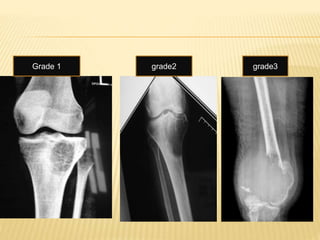

 Campanacci Grading:

 Grade I: Tumour associated with well defined

margins and thin rim of mature bone [cystic

lesion]

 Grade II: Tumour is well defined but has no

radiopaque rim[thin cortex but no break in

cortex]

 Grade III: Tumour has fuzzy borders [cortex

break & soft tissue extension]

Grade 1 grade2 grade3